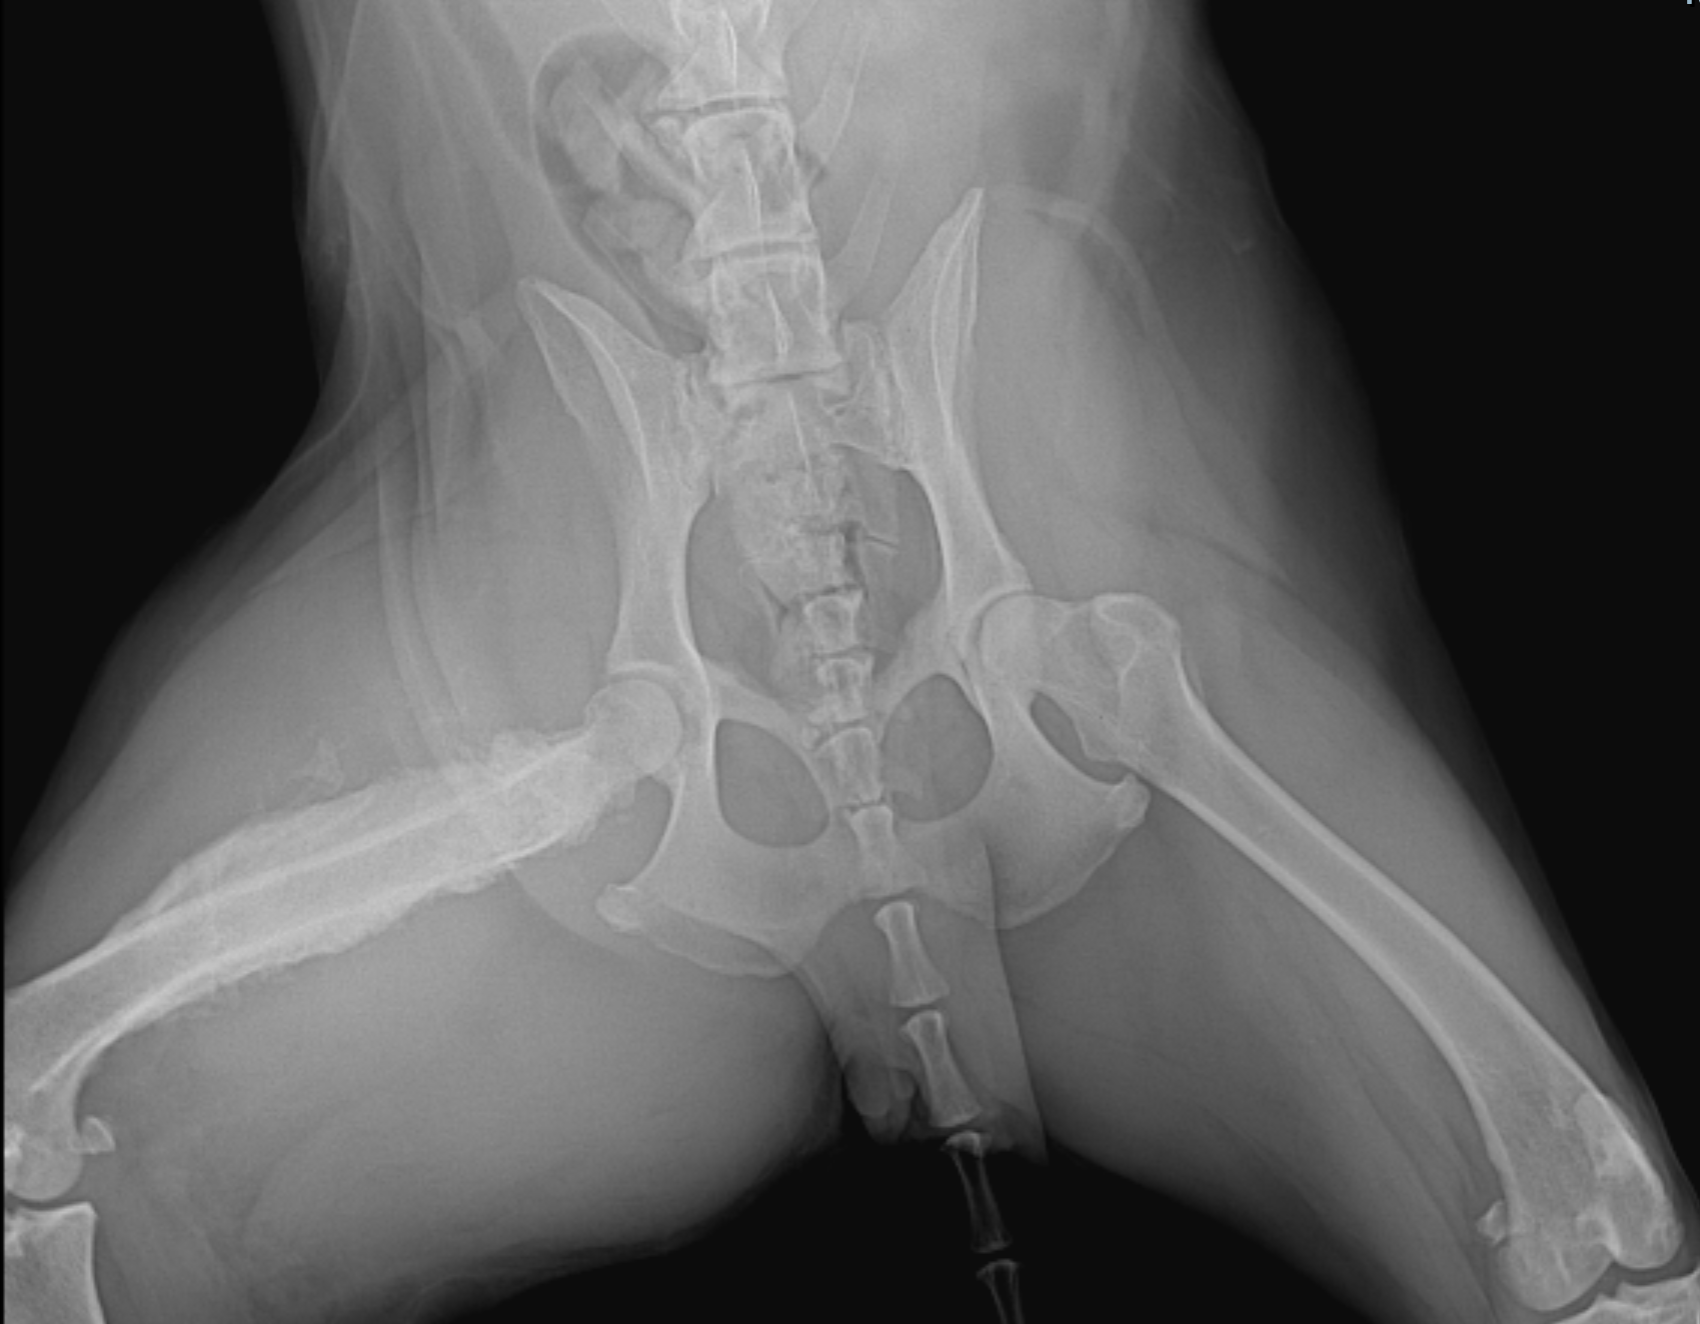

Core staging components remain familiar: CBC, chemistry, urinalysis, retroviral testing in cats, regional lymph node cytology, thoracic radiographs, abdominal ultrasound, and advanced imaging (CT or MRI) when clinically indicated. IHC, flow cytometry, and PARR continue to add diagnostic and prognostic value for lymphoid neoplasia.